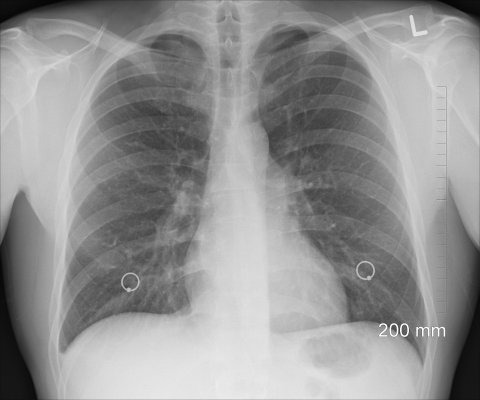

Alta ingesta de líquidos, descanso reparador, alimentación rica en nutrientes para fortalecer el sistema inmunológico, aplicación de vacunas contra el neumococo e influenza, son las principales recomendaciones para evitar la neumonía, padecimiento que afecta directamente a los pulmones.

El doctor Aguilar Sánchez refirió que la enfermedad se caracteriza por la inflamación del tejido pulmonar, producto de una infección adquirida fuera del ámbito hospitalario. Se transmite a través del aire por secreciones procedentes de nariz, garganta o bronquios que arroja una persona portadora de los virus, bacterias u hongos que la provocan.